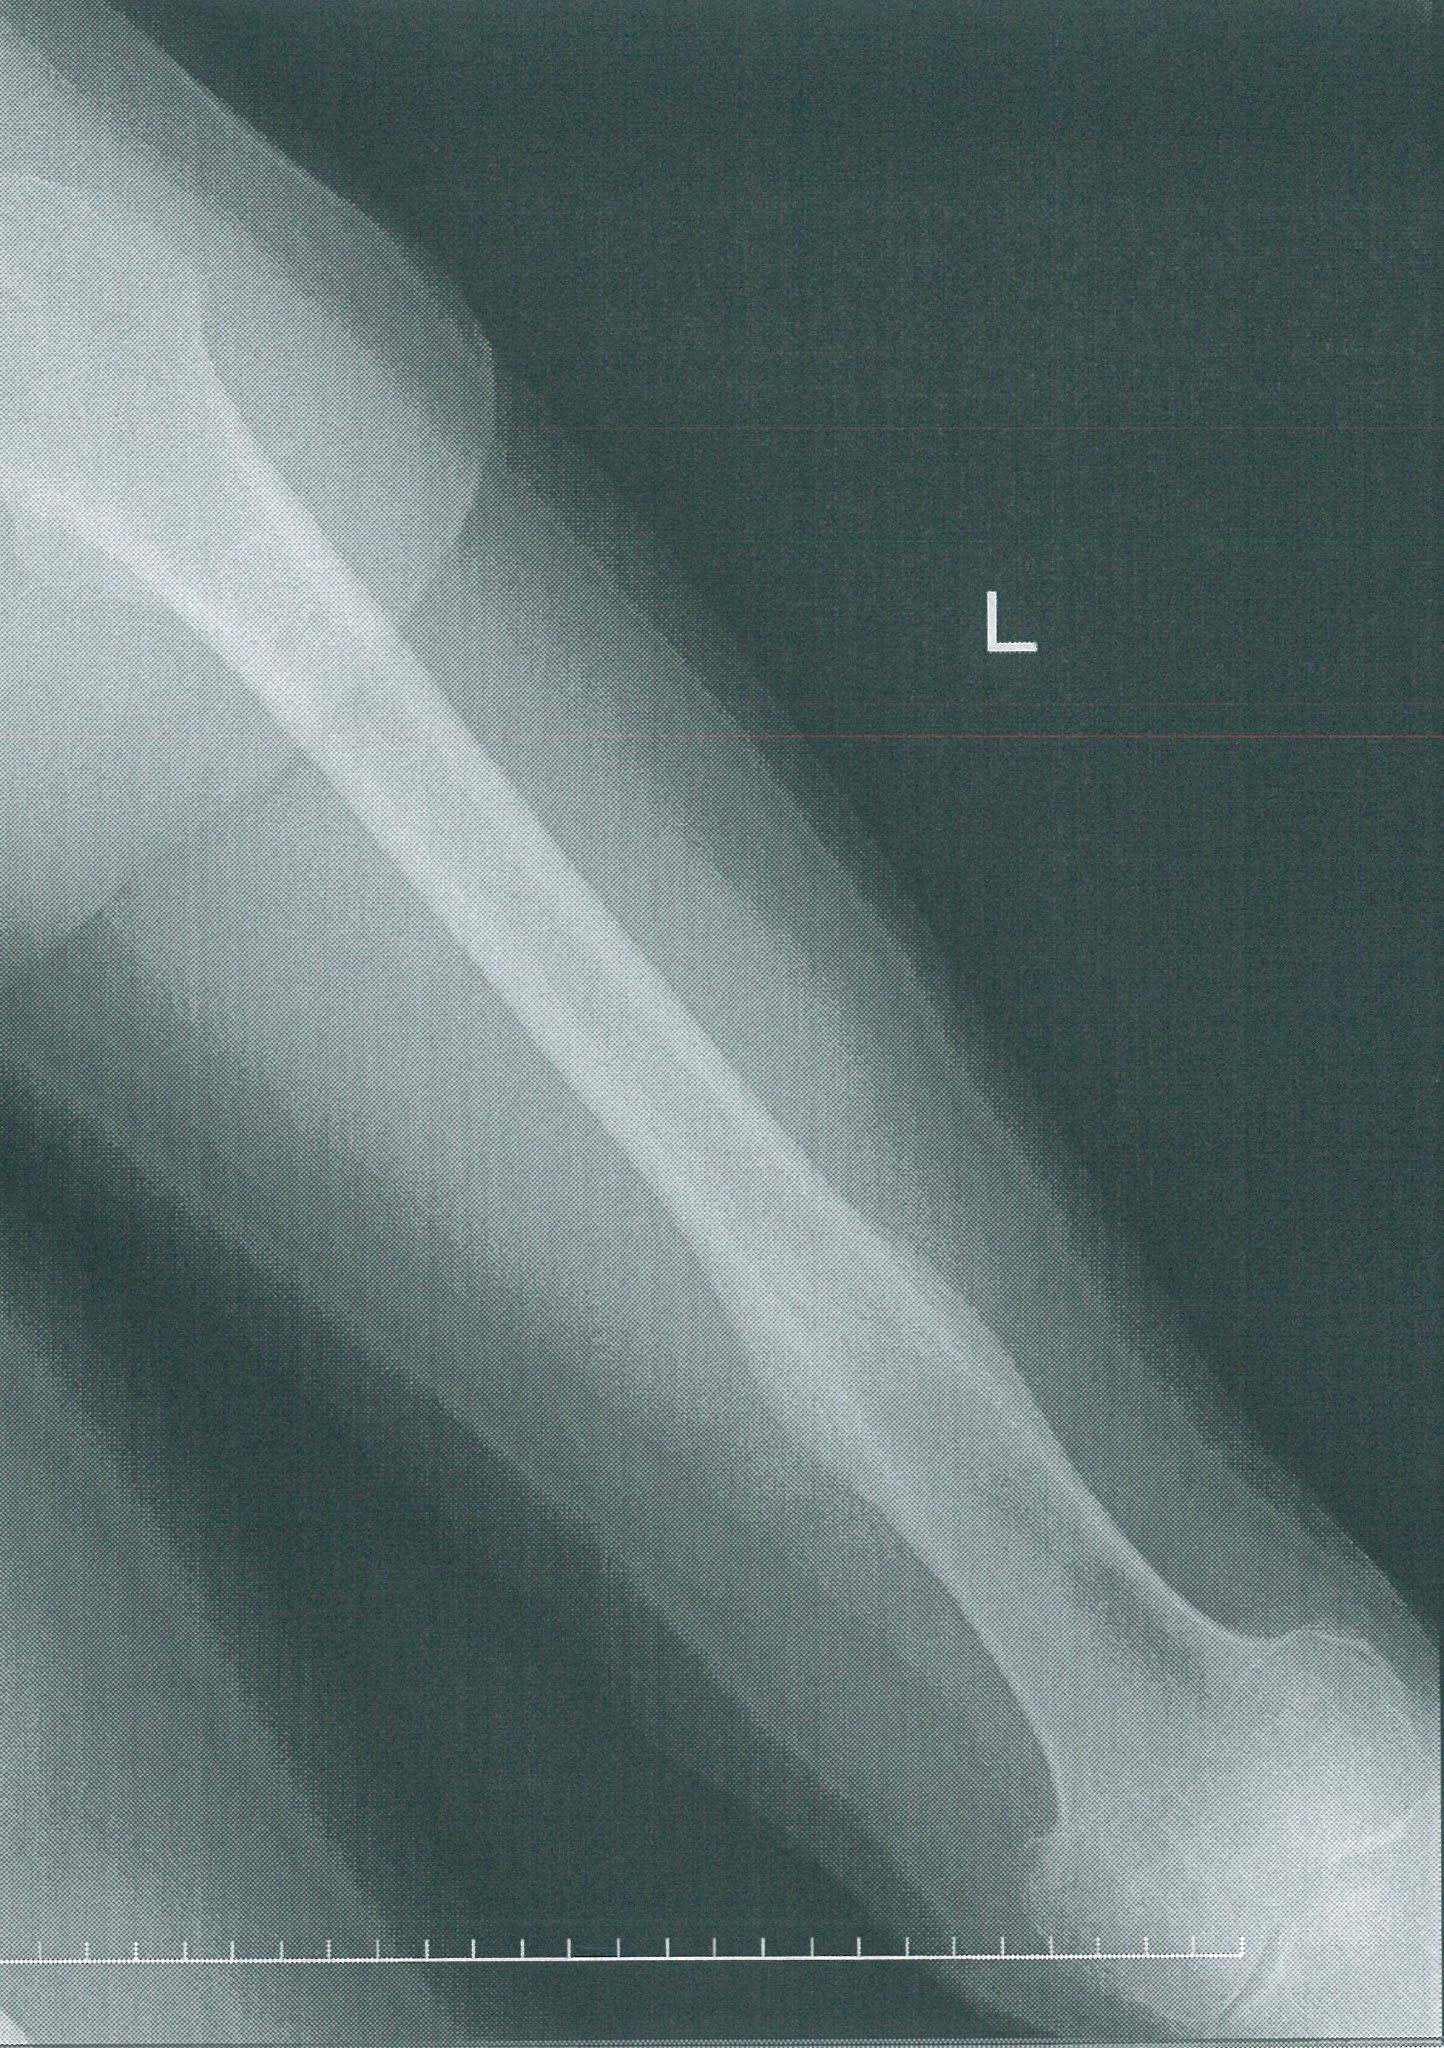

右大腿骨骨折,両前腕骨骨折のためにギプス固定をし ている。安静度はギャッヂベッド挙上30度のみ許可さ れている。指示食:五分粥食 2)食事援助の実際(表1参照) 二人一組で看護師役と患者役を交代し,事例①・②の転んだり、強くぶつけたりした時に手を打って、それから痛みが引かない場合、骨折の可能性があります。 日常的によく使う手を骨折すると不便なものです。 できるだけ早く治したいですよね。 骨折した時はどのようなことに気をつければいいのでしょうか?

3 歳の女性 右利き 手関節脱臼骨折後 手関節掌屈0 前腕回外10 の可動域制限がある スタディメディマール